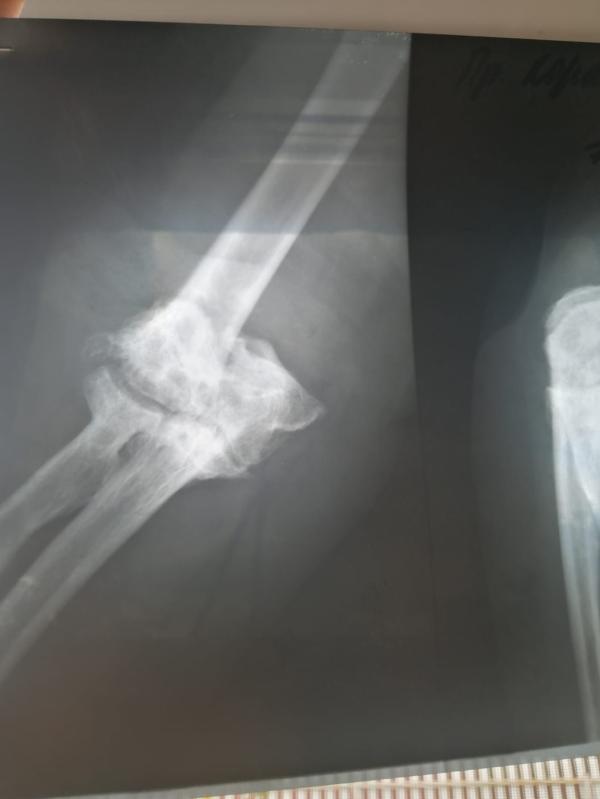

Такая история, бабушка вчера упала, сломала руку, поставили диагноз закрытый оскольчатый перелом мыщелков правого плеча со смещением. Операцию делать не стали, бабушке 85 лет, наложили лангетку и отпустили домой. Вопрос, а как там может все без вправления и спиц сростись?

Теперь вижу снимок, а не только назначения. Криво срастётся, если репозицию не делать. Я бы бабушку отвезла в Бурденко или Боткинскую к травматологу